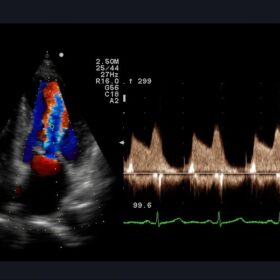

Ultrasound Aloka Prosound Alpha 10 – Image Gallery and Videos

Enhanced image quality ensures more accurate and efficient diagnosis while increasing patient satisfaction. The ideal choice for a large office or hospital imaging department. The Alpha 10 combines a 12 Bit A/D digital beam converter. High powered image processing channels and the exclusive probe technology to take examinations to the next level.

Sophisticated beam control provides high resolution and penetration while minimizing image degradation. While user-oriented operability and ergonomics create the ideal environment for fast and accurate imaging and diagnoses. The Alpha 10’s Extended Pure Harmonic Detection is a digital pure beam-imaging platform. That incorporates state-of-the-art acoustic technology that dramatically improves the clarity of the ultrasound beam formation and signal processing.

Striving to eliminate undesirable sound components from the transmitted ultrasound beam itself and with the ever-evolving ProSound technologies ALOKA has created the ProSound A10 platform. With its Ultimate Compounding Technologies, stress-free operation and combination of versatility and performance, the Aloka Prosound Alpha 10 provides the capability for a wide range of sophisticated diagnoses.

- Compound Pulse Wave Generator allows us to actually design the transmission waveform for individual application. The clear waveform enhances focus accuracy, spatial and contrast resolution, while reducing artifacts.